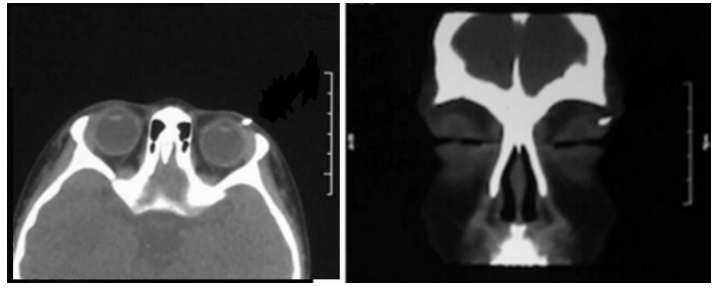

初步诊断:1)左眼先天性泪腺皮肤瘘;2)左眼上睑毛发异位。患儿病情复杂,为明确诊断,为患儿行在全身麻醉下行左眼泪腺瘘管数字减影检查,结果显示左眼泪腺瘘管造影剂存留,瘘管深部存在扇形腔隙(图2)。并行泪腺瘘管CT造影检查,行眼眶CT水平+冠状位扫描,泪腺瘘管CT造影结果显示左眼外侧泪腺高密度影(图3)。后予患儿全身麻醉下行左眼泪腺皮肤瘘管探查+异位毛发病灶切除+泪腺瘘管转位结膜囊吻合代泪腺导管术。患儿取仰卧位,全身麻醉起效后,常规用75%酒精消毒左眼周围皮肤,铺无菌手术巾。自泪腺瘘管皮肤面注入亚甲蓝标记瘘管,瘘管内插入冲洗针,翻转眼睑,暴露穹隆结膜,冲洗针引导下横行切开穹隆结膜3 mm。沿左上睑瘘口周围做梭形皮肤切口,钝性分离瘘管周围组织,术中发现瘘管基底部呈扇形,内表层为上皮组织,见毛囊及较多毛发,且有一大小约为3 mm×3 mm×2 mm的异位泪腺组织,其与瘘管相连,瘘管的另一端与正常泪腺导管相连。完整切除皮肤到异位泪腺之间的瘘管和异位泪腺及异位毛发病灶,切除的病变组织(图4)送病理检查。将正常泪腺导管用8/0可吸收线固定缝合于颞上穹隆结膜,导管内置引流条1根,引流条以8-0线固定缝合于睑结膜表面,6-0丝线间断缝合皮肤切口。术毕,予患儿左眼戴角膜绷带镜,绷带加压包扎左眼。手术顺利,切口愈合好,术后2 d打开加压包扎(图6)观察,患儿左眼上睑皮肤无明显红肿,无渗血、渗液,切口对合好,缝线在位,泪腺导管引流条在位,术后 7 d 拆除缝线,取出泪腺导管引流条。术后病理报告确诊左眼先天性泪腺皮肤瘘管伴毛发异位,异位泪腺(图5)。患儿于2022年9月22日出院。术后1个月返院复查,结膜吻合口和皮肤切口愈合好(图7),转位的泪腺瘘管成功将泪液引流入上穹隆结膜囊内。术后随访1年,未见瘘管复发。

图 3 泪腺瘘管CT造影结果

Figure 3 CT results of lacrimal fistula

左眼泪腺高密度影(橙色箭头)。It showed high density of lacrimal gland in left eye(orange arrow).